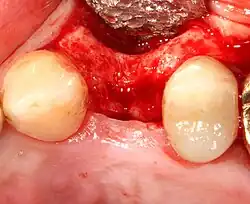

Восстановление мягких тканей

При утрате одного или нескольких зубов костная ткань в этом месте со временем истончается из-за отсутствия жевательной нагрузки, что ведёт к деформации челюстно-лицевой системы. Наличие имплантата обеспечивает адекватную нагрузку на кость челюсти подобно естественному корню зуба, поэтому истончения костной ткани не происходит. Каждый человек, который потерял один или несколько зубов в результате различных травм, болезней или разрушения зубов, имеют показания для имплантации зубов. Люди преклонного возраста также могут пройти процедуру имплантации, поскольку определяющим фактором её осуществления является скорее состояние здоровья, нежели возраст. Вопрос о том, возможно ли проведение дентальной имплантации, решается специалистом — стоматологом после тщательного медицинского обследования конкретного пациента и детального осмотра состояния его зубов.